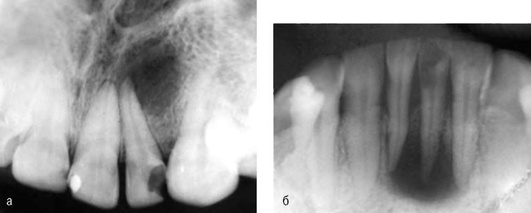

Вокруг участка разрежения можно видеть плотное губчатое вещество костной ткани. При обострении процесса гранулема может принимать нечёткие контуры. Благоприятным исходом при своевременном и правильно проведённом лечении считают регрессию очага деструкции и восстановление костной ткани. Отсутствие или неправильное лечение могут привести к увеличению очага воспаления и резорбции кости с развитием радикулярной кисты (рис. 13-9).

image

Рис. 13-9. Внутриротовые рентгенограммы: а - деструкция костной ткани у верхушки корня зуба 35 (как исход некачественного эндодонтического лечения); б - деструкция костной ткани у верхушки зуба 22

Рентгенологическую картину характеризует деструкция тканей у верхушки корня, где образуются различных размеров очаги разрежения костной ткани без четких границ (рис. 13-10).

Рис. 13-10. Внутриротовая рентгенограмма. Деструкциия костной ткани с нечеткими контурами у верхушек корней зубов 14, 15